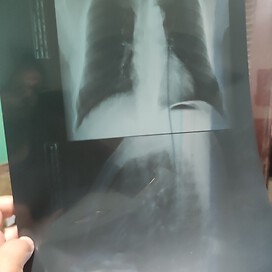

The chest X ray tells bilateral accentuated lung vascularity

does it mean I am diagnosis of copd?